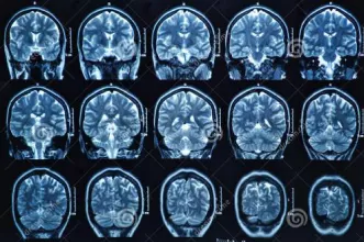

MRI也就是磁共振成像,属于断层成像的一种,它是利用磁共振现象从人体中获得电磁信号,并重建出人体信息。通过检查可获得横断面、矢状面、冠状面的影像,空间分辨率高,是神经系统、脊柱脊椎部分检测的第一选择。

无论是DR还是CT,由于对部分软组织的分辨率不足,所以软组织疾病的排查便成了它们的短板,而磁共振的长处恰恰就是清晰显示软组织疾病,对于膀胱、直肠、子宫及关节肌肉的检查优于CT。MRI适用于神经系统病变、心血管系统、胸部病变、全身软组织病变等。